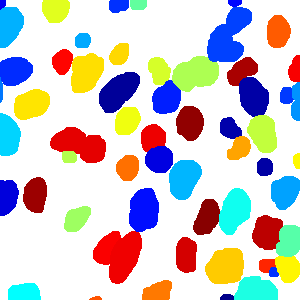

The task of nuclei segmentation can be roughly divided into two stages: the first stage is extracting the foreground(nuclei), the second stage is segmenting the connected foreground area into separated nuclei and finding out the boundary of each nucleus. Our method intends to merge these two steps by extracting the nuclei and their edges at the same time. That is the reason why it is named ”nuclei-boundary(NB) model”. As shown in Fig.3, the output of the NB model has three channels, each has the same height and width with the input image. Its values represent the probabilities of each pixel being , or class, respectively. The manual annotation for our segmentation problem is the boundary of each nucleus. A pixel belonging to the class means that it is on or inside an annotated boundary and within 2 pixel from the boundary. Pixels of the class are those that are inside annotated boundary but are not pixels. Correspondingly, the output can be regarded as an RGB image and the estimated maps of the , and are represented by red, green and blue, respectively, as shown in Fig.3. To generate the ternary mask for training, we apply a morphology operator to each nucleus to obtain the pixels, and then subtract pixels from the nucleus to get pixels.

Figure 6 shows how our method segments the nuclei step by step. The color variety is well controlled by the color normalization procedure. The prediction result shows clear nuclear areas and nucleus boundaries. In the final segmentation result and ground truth image, each nucleus is represented by a different color.